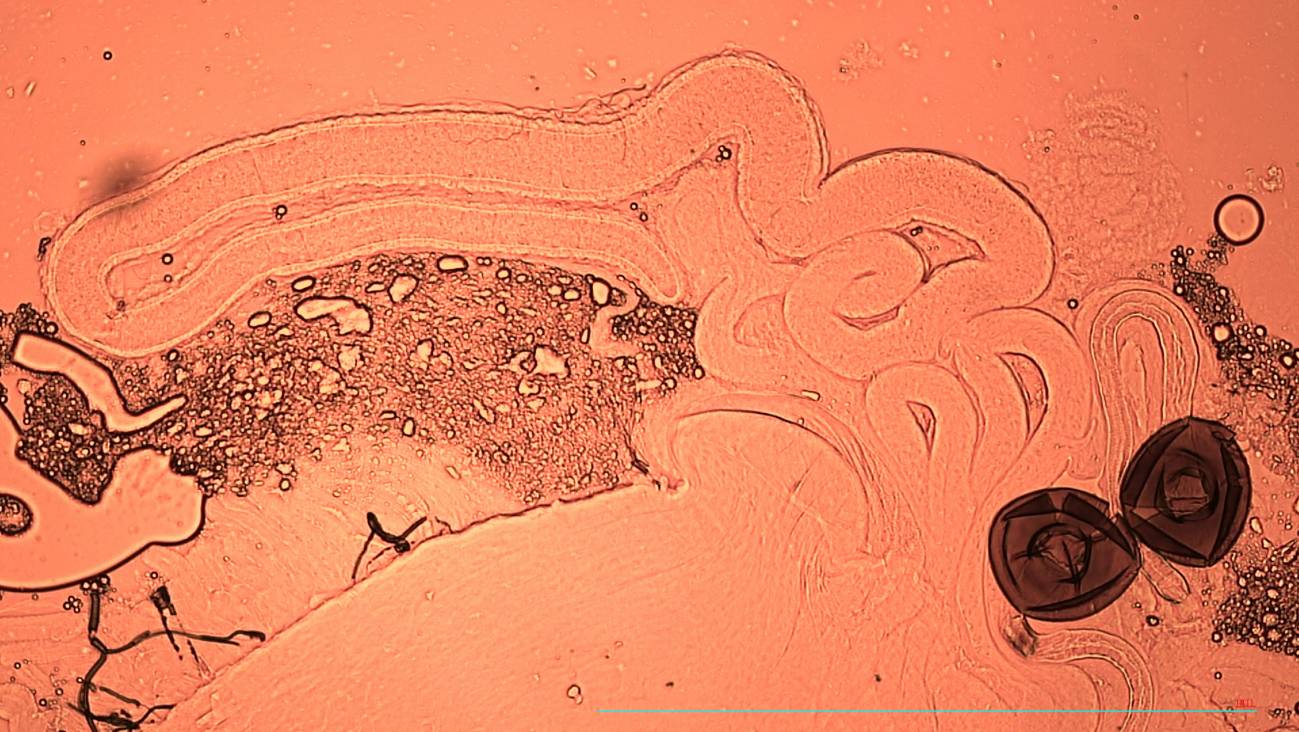

Esperma en las espermatecas (órgano especializado en almacenamiento de esperma a largo plazo) de una mosca hembra de la fruta. / Krish Sangvhi

Según expone la coautora del trabajo e investigadora en la institución inglesa, Rebecca Dean, varias hembras de insectos, aves y reptiles son capaces almacenar semen durante semanas o años gracias a órganos especializados que nutren los espermatozoides con proteínas y antioxidantes que reducen su deterioro.